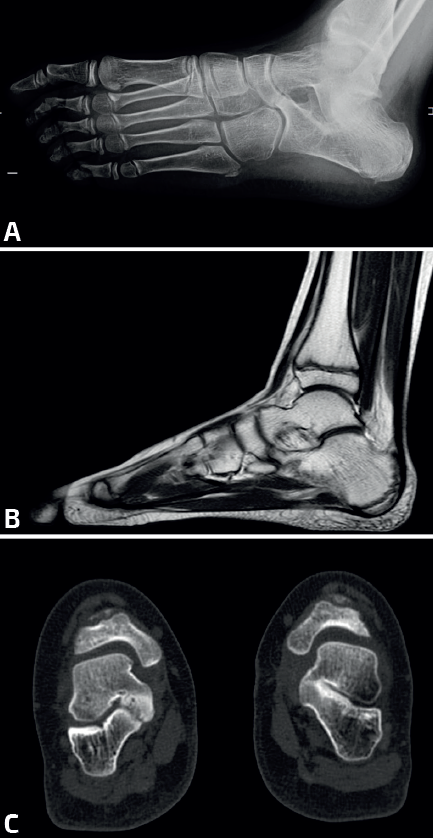

Evolutivamente, estas coaliciones pueden causar una deformidad del pie en plano valgo(3)(Figura 1), aunque también se han descrito, con menor frecuencia, casos de pie cavo varo(4). Este tipo de deformidad es también conocida como pie plano rígido o pie plano espástico peroneo.

Es la primera prueba complementaria indicada en un paciente con sospecha de coalición tarsal. Las proyecciones básicas incluyen la dorsoplantar y lateral de los pies en carga, una oblicua a 45° y la proyección de Harris-Beath. Además, es importante realizar una radiografía en carga del tobillo. La mayoría de las coaliciones tarsales se pueden diagnosticar mediante radiografías simples, con la excepción de la CA, que precisa realizar una tomografía computarizada (TC) o una resonancia magnética (RM) para una visualización adecuada.

Proyección oblicua del pie a 45° (Figura 3A).

La CE se visualiza mejor en esta proyección, que presenta una sensibilidad del 90-100%. En condiciones normales, estos huesos no articulan entre sí, por lo que cualquier unión es altamente sugestiva de coalición. En las coaliciones óseas, se objetiva una unión completa con una prolongación del escafoides hacia el calcáneo, mientras que en las coaliciones fibrocartilaginosas se aprecia una disminución del espacio entre ambos huesos con bordes esclerosos e irregulares (pseudoarticulación).

La RM se está utilizando cada vez con mayor frecuencia, sobre todo en pacientes más jóvenes, en los que las coaliciones suelen ser fibrocartilaginosas. Esta técnica evita la exposición a radiaciones ionizantes, pero puede requerir anestesia general en niños pequeños debido al mayor tiempo necesario para su realización. Permite visualizar edema de la médula ósea, orientación anómala de la articulación y aplanamiento de la superficie articular. En coaliciones óseas se objetiva una imagen de la medular continua entre ambos huesos (Figura 3B)(7).

La TC ofrece imágenes en los planos sagital, coronal y transversal, así como reconstrucciones en 3D, siendo las proyecciones coronales las más informativas. Cualquier irregularidad en la carilla articular media entre el calcáneo y el astrágalo es sugestiva de coalición. Además, la TC permite medir el valgo del retropié, evaluando el ángulo formado entre la línea perpendicular del eje de la articulación del tobillo y la línea del eje del calcáneo. Un ángulo mayor de 16° se considera indicativo de un valgo aumentado (Figura 3C)(8).